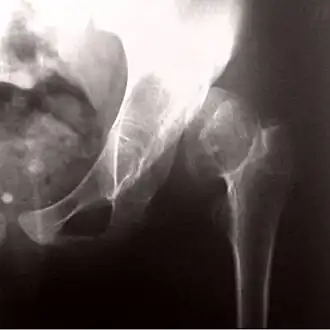

Патологический вывих бедра и неоартроз при врождённом вывихе бедра

Если вывих бедренной кости не устранён, то, следуя известному биологическому закону «функция определяет форму», растущие кости таза и бедренная кость изменяются, приспосабливаясь к новым условиям нагрузки. Головка бедренной кости теряет обычную шаровидную форму и уплощается. Пустая вертлужная впадина уменьшается в размерах, а в месте нового расположения головки бедренной кости (в области крыла подвздошной кости) формируется новая суставная впадина. Вновь образованный сустав называют «неоартроз» – неполноценный сустав, однако он десятки лет «служит» тем пациентам, у которых по разным причинам не был устранён врождённый вывих бедра.

При неправильном лечении врождённого вывиха бедра в детском возрасте бедренная кость смещается вверх за пределы вертлужной впадины и упирается в тазовую кость.

«В этом месте образуется новая впадина – "впадина вывиха". Эта впадина делается глубокой из-за развивающегося в ней костного выступа и хорошо удерживает головку от дальнейшего смещения вверх. До известной степени это является самоизлечением.»[27]

Образуется новый сустав (неоартроз). Нередко неоартроз сочетается с патологическим вывихом бедра. Неоартроз сочетается с анатомическим и функциональным укорочением бедра и резким снижением функции отводящих бедро мышц. Функционально это достаточно полноценный сустав, позволяющий выполнение бытовых движений и ходьбы (при компенсации укорочения, которая характеризуется классическим синдромом Тренделенбурга). В современной ортопедической практике встречается крайне редко.